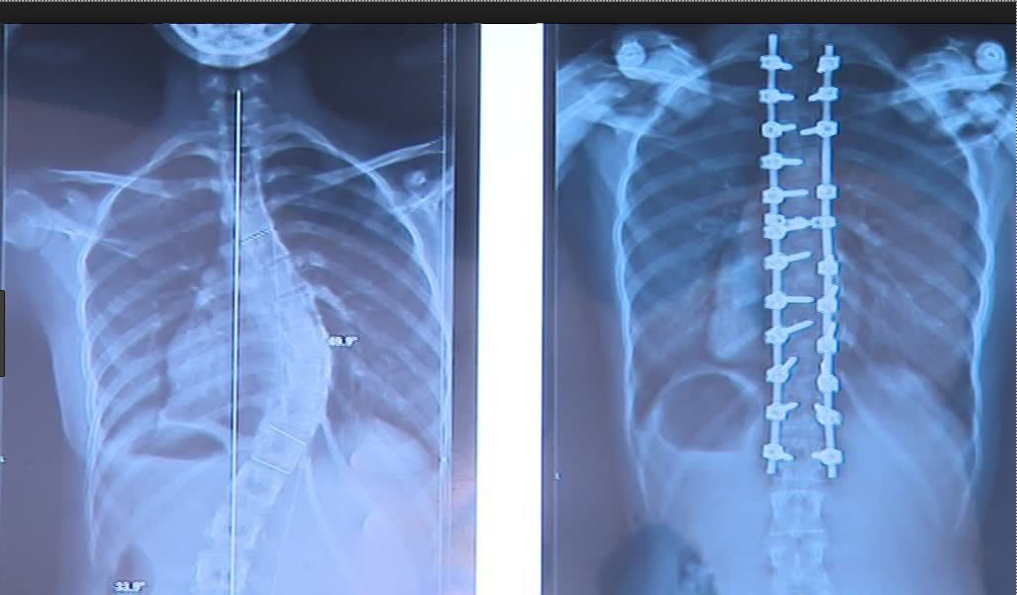

Radiographie standard: Scoliose avant après intervention par arthrodèse

Dans les cas graves, la scoliose peut évoluer avec le temps. Dans ces cas, le médecin peut recommander une fusion vertébrale ou arthrodèse vertébrale. Cette opération réduit la courbe de la colonne vertébrale et l'empêche de s'aggraver.

Fusion vertébrale (ou arthrodèse) avec greffes osseuses: deux ou plusieurs vertèbres (os de la colonne vertébrale) sont associées à de nouvelles greffes osseuses. Parfois, des tiges de métal, des crochets, des vis ou des fils sont utilisés pour maintenir une partie de la colonne vertébrale bien droite pendant que l'os guérit.